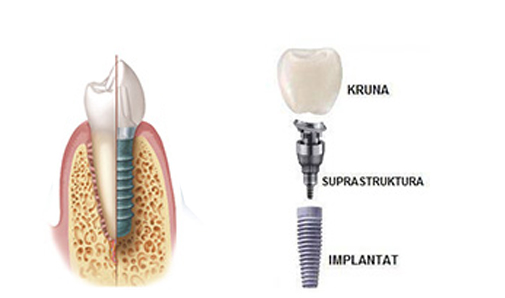

- Online zakazivanjeZubni implant se sastoji iz tri cjeline:

- Titanijumskog vještačkog zubnog korjena koji se ubacuje u viličnu kost;

- Nadogradnje koja se fiksira u titanijumski korjen;

- Krunice koja se postavlja na nadogradnju.

Na taj način zubni implant u potpunosti zamjenjuje izgubljeni zub. Implant postaje replika nekadašnjeg zuba. Procedura za implantiranje zuba je jednostavna. Na početku potrebno je izvršiti rendgensko snimanje vilice, kako bi se utvrdilo da li ima dovoljno koštane mase u vilici. Ako nema, pre implantiranja vrši se operacija ugradnje vještačke kosti. Sama operacija ugradnje implantata traje oko 30 minuta. Nakon završene operacije čeka se 3 mjeseca da implant uraste u viličnu kost. Tek nakon tog perioda pacijent dolazi ponovo u ordinaciju gdje mu se na implant fiksira nadograđena struktura (supra struktura) i vrši izrada protetskih nadoknada (krunica).